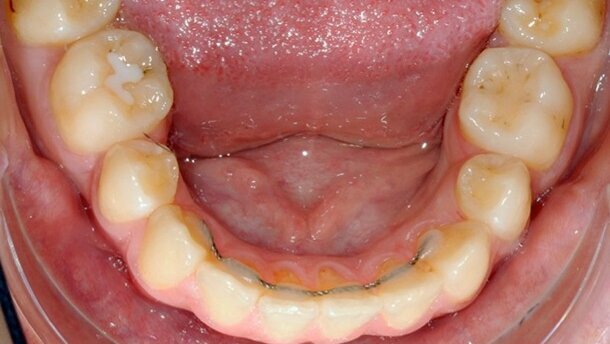

Le retrait de la gouttière est aisé, le fil reste collé sur les dents (Fig. 12).